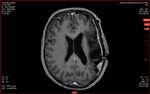

26.01.2025: Gamma-Knife

Es werden  die folgenden Meningeome therapiert:

• #2 Konvexitätsmeningeom links temporalateral (8 x 5 x 7 mm)

• #3 Links tempora-medial ausgehend vom Tentorium unmittelbar oberhalb des Cavum Meckeli links (10 x 10 x 11 mm) Minimum

• #4 Links temporo- okzipital im okzipito parietalen Übergang (20 x 11 x 13 mm)

• #6 Links okzipito lateral (8 mm unterhalb von #4)

26.01.2025: Diagnose

Die Aufnahme zeigt erstmalig eine durale Verdickung im Sinne eines weiteren Meningeoms links hochparietal mit einem Durchmesser von 26 x 6 x 22 mm. Diese durale Verdickung ist am26.01.2025 nicht behandelt worden, da dies zu stark belastet hätte.

Darüber hinaus handelt es sich hier um ein eher flächiges Meningeom, wobei geklärt werden sollte, ob dieser Tumor fraktioniert bestrahlt werden soll.